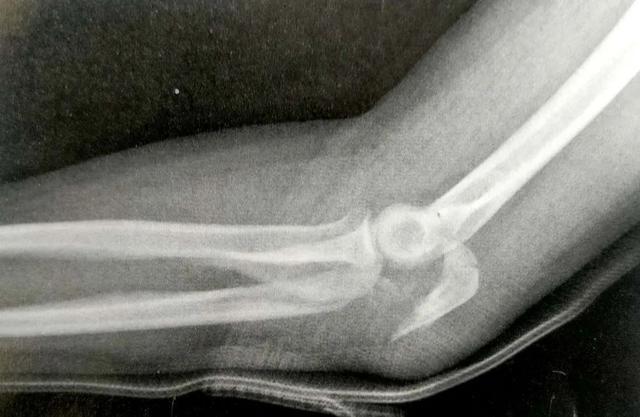

A:鹰嘴的骨折脱位

B-C:用低切迹钢板固定

生物力学测试发现,在横行骨折中,钢板明显比张力带更能提供压缩应力。重建钢板和1/3管型也取得了一些成功,但我们不推荐使用。伤口并发症是使用钢板时最需要关心的问题,因为尺骨近端的软组织覆盖欠佳,以及肘关节屈曲时后侧软组织存在张力。